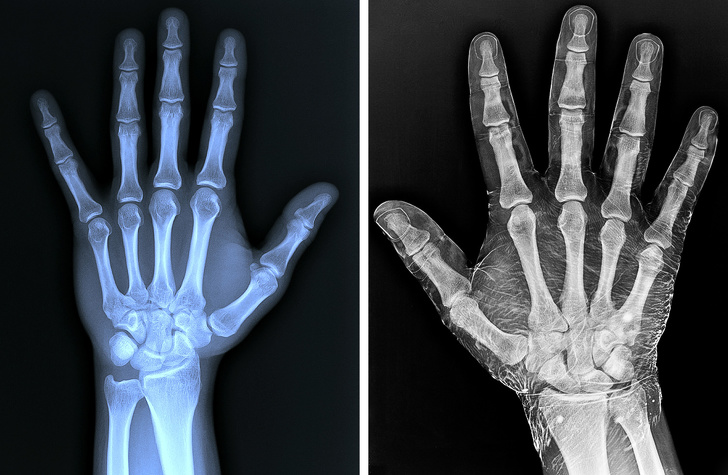

8. Рентгенограма кисті: зліва — звичайний знімок, рука праворуч полита йодом

У рентгенології речовини на основі йоду використовуються в якості контрасту.